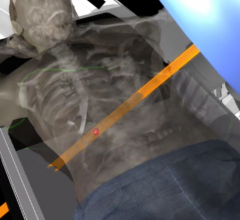

Together with physicians, other research groups, and industry partners, Fraunhofer MEVIS is developing software to optimize radiation therapy. The fifth clinical workshop to evaluate this software took place in Bremen on Feb. 5-6.